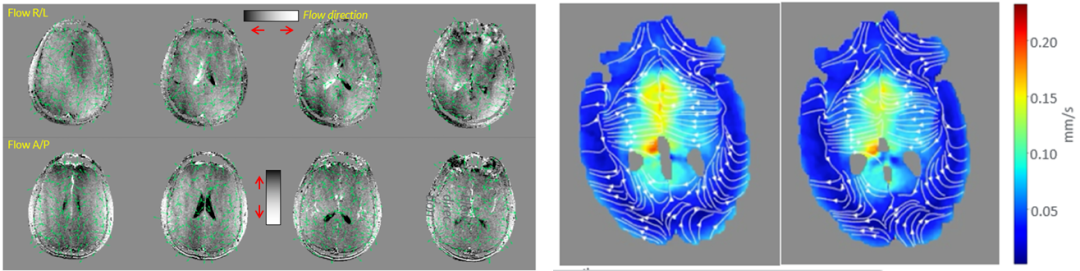

类淋巴系统可视化:脑类淋巴系统清除功能受损,可能导致并加重病理性毒性蛋白的沉积,诱发或加剧AD,PD等退行性病变的症状。类淋巴系统类似微循环系统,流动交换速率约为0.1-5mm/s,流速极慢难以捕捉信号。

在GE医疗与犹他州立大学的合作中,利用SIGNA MAGNUS成功绘制出全脑的类淋巴通路,并且证实了结果与痴呆电生理结果的吻合性,为微脑疾病的研究提供了全新思路。